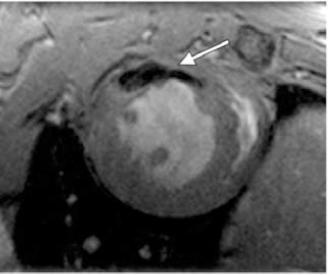

Cardiovascular magnetic resonance (CMR) imaging is the modality of choice for clinical studies of the heart and vasculature, offering detailed images of both structure and function with high temporal resolution.Small animals are increasingly used for genetic and translational research, in conjunction with models of common pathologies such as myocardial infarction. In all cases, effective methods for characterising a wide range of functional and anatomical parameters are crucial for robust studies.CMR is the gold-standard for the non-invasive examination of these models, although physiological differences, such as rapid heart rate, make this a greater challenge than conventional clinical imaging. However, with the help of specialised magnetic resonance (MR) systems, novel gating strategies and optimised pulse sequences, high-quality images can be obtained in these animals despite their small size. In this review, we provide an overview of the principal CMR techniques for small animals for example cine, angiography and perfusion imaging, which can provide measures such as ejection fraction, vessel anatomy and local blood flow, respectively. In combination with MR contrast agents, regional dysfunction in the heart can also be identified and assessed. We also discuss optimal methods for analysing CMR data, particularly the use of semi-automated tools for parameter measurement to reduce analysis time. Finally, we describe current and emerging methods for imaging the developing heart, aiding characterisation of congenital cardiovascular defects. Advanced small animal CMR now offers an unparalleled range of cardiovascular assessments. Employing these methods should allow new insights into the structural, functional and molecular basis of the cardiovascular system.

心血管磁共振(CMR)成像技术是心脏和血管临床研究的首选方式,能够以高时间分辨率提供心脏结构和功能的详细图像。越来越多的小动物被用于基因和转化研究,并与诸如心肌梗死等常见病理模型相结合。在所有情况下,有效表征各种功能和解剖参数的方法对于可靠的研究至关重要。CMR是这些模型无创检查的金标准,尽管诸如心率过快等生理差异使得这项工作比传统临床成像更具挑战性。然而,借助专门的磁共振(MR)系统、新颖的门控策略和优化的脉冲序列,尽管动物体型小,仍可在这些动物身上获得高质量图像。在本综述中,我们概述了用于小动物的主要CMR技术,例如电影成像、血管造影和灌注成像,它们可分别提供诸如射血分数、血管解剖结构和局部血流等测量值。结合MR造影剂,还可识别和评估心脏局部功能障碍。我们还讨论了分析CMR数据的最佳方法,特别是使用半自动工具进行参数测量以减少分析时间。最后,我们描述了当前和新兴的用于发育中心脏成像的方法,有助于先天性心血管缺陷的特征描述。先进的小动物CMR现在提供了无与伦比的一系列心血管评估。采用这些方法应该能够对心血管系统的结构、功能和分子基础有新的认识。